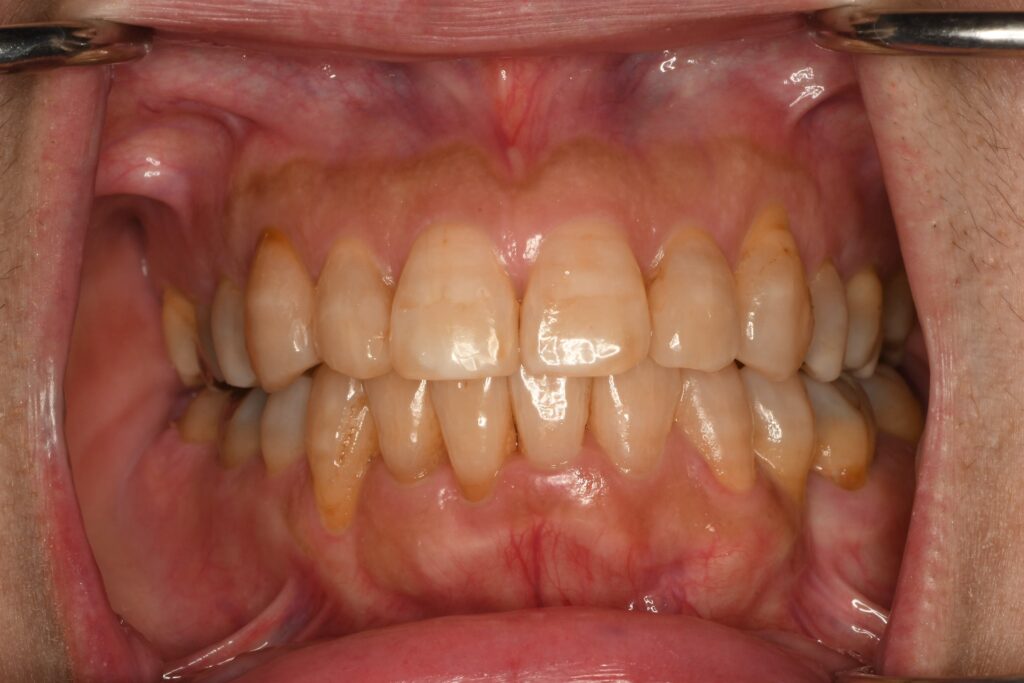

50代・女性

前歯の並び方や奥歯の噛み合わせなど、満足できるまで治療を受けさせていただいて、誠に有難う御座いました。

歯並びが綺麗に揃ったことで気が付いたことは、歯磨きがとても楽になりました。以前は凸凹していたため、歯ブラシをあっちこっちに向けて磨いていたので、ブラシ部分がすぐにボロボロになってましたが、今はかなり長持ちするようになりました。

一番嬉しいことは、歯を見せて笑うことに抵抗が無くなったことです。凹凸が解消されたからか、なんとなく色が白くなった?ような気もしています。

当初の予定の倍以上の期間をかけましたが、本人の満足度も高まって良かったです。